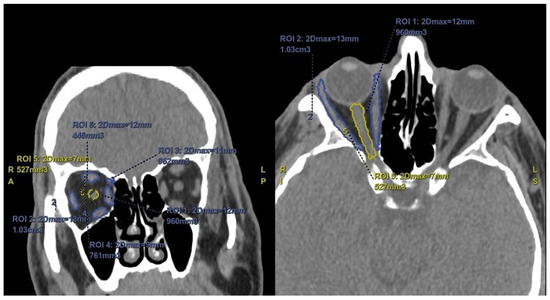

Two radiologists with 10 years and 11 years of experience performed the radiological evaluations of the patients, blinded to their clinical characteristics. The measurements of the first radiologist were accepted as the study data. To test the repeatability of the measurements, a second radiologist with 11 years of experience repeated the same measurements. Enophthalmos measurements were performed on axial section images of the CT. For this evaluation, an interzygomatic horizontal line was drawn on the axial section, and the distances of the corneal edge to this horizontal line were measured anteriorly. Additionally, volume measurements of the orbital fat, periorbital muscles, and optic nerve were performed. Using the software on the workstation (AW Server 4.7 by GE Healthcare, Milwaukee, WI, USA), the radiologists manually marked the free regions of interest (ROI) for orbital fat tissue, periorbital muscles, and optic nerve separately in both eyes on sagittal, coronal, and axial sections, and three-dimensional volume measurements were performed (Figure 1).

Figure 1. Coronal and axial sections with manual region of interest (ROI) for muscle and optic nerve volume measurements.